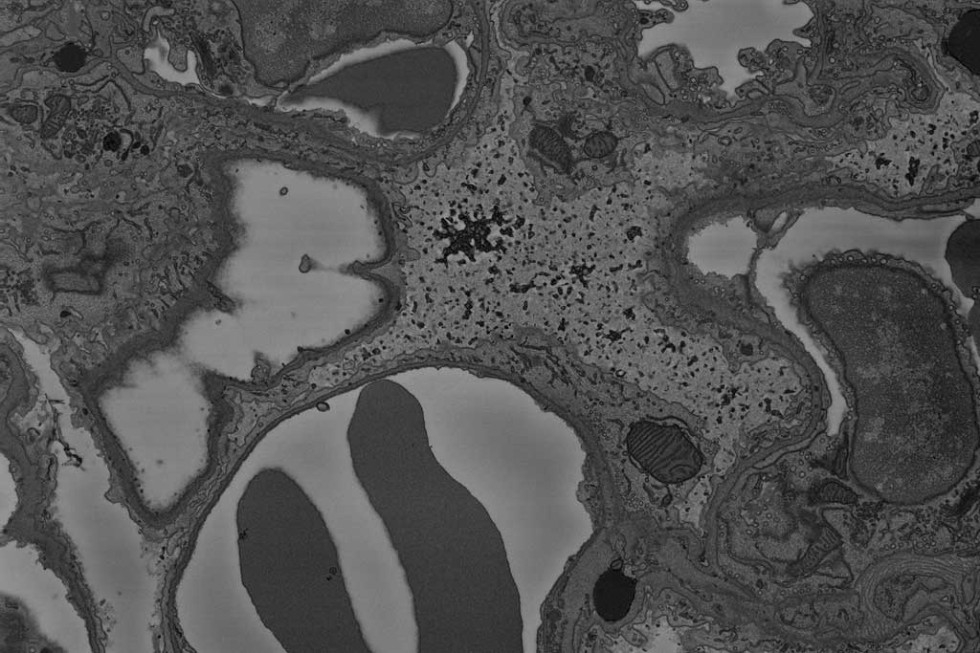

GeminiSEM 300 / 450可无缝结合Gatan公司的3View®技术,变身成为快速且高质量获取包埋细胞或组织样品的高分辨率三维数据的一套系统。3View®是扫描电子显微镜样品室内的一台超微切片机,与蔡司GeminiSEM系列产品成像快速、样品灵活、视野大且无畸变的技术特点结合,该系统能在一天内对样品进行数千个连续切片和自动高质量成像,有效的节省了时间。因为样品保持固定不动,所获取的图像具有更高的重合度,使得重构得出的三维数据更为高效和真实还原样品的三维结构。

现在,搭载蔡司局部电荷中和器技术的GeminiSEM可以更好地消除以往富有挑战的不导电样品的表面荷电,进一步提高生物组织切片样品,如肝脏、肾脏、肺部等组织切片图像的质量,以更好地帮助科学家们进行病理学等相关领域的生命科学研究。蔡司公司已经把这套目前更快更简便而且具有更高质量的三维成像系统提供给了德国国家显微成像中心,并将与之开展长期合作和取得共赢。